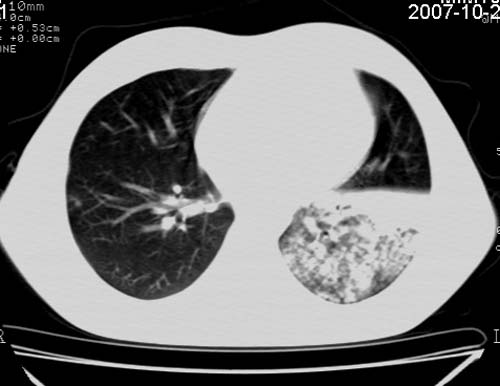

男,21岁,咳嗽、胸闷、乏力伴多汗二十余日、无明显发烧。患者一般情况好,为初三学生。

右肺上叶前段及左肺下叶多形性病变伴厚壁空洞,周边示树芽征.左肺下叶不张改变.

考虑;肺结核,不除外左肺下叶支气管内膜结核.

双肺继发性肺结核伴左侧空洞形成!不除外合并霉菌感染!(双肺多发病灶,左侧病灶形成空洞,并空洞内见壁结节。建议改变体位,观察空洞内结节情况,以便排除霉菌感染!)

结核并支气管播散

左下肺实变能给出合理解释吗?